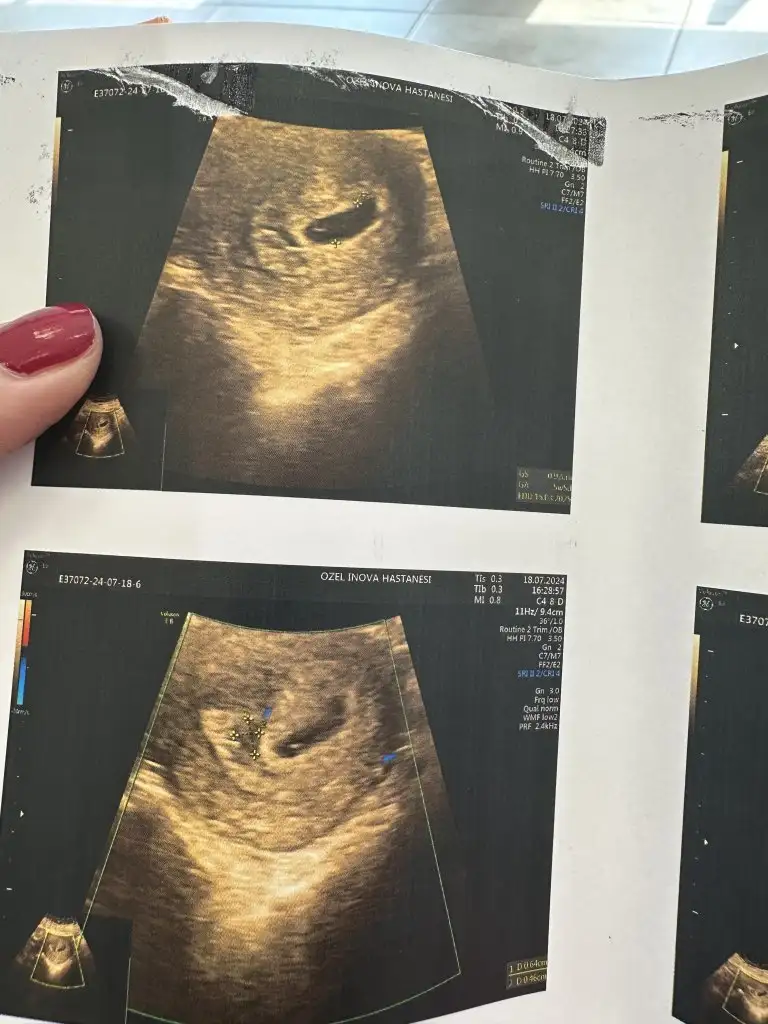

aa çok sevındım. bu kadar erken cınsıyet söylerim diyen dr pek çıkmaz. ben dun verdim o kanı ınsallah sonuclarımız guzel gelirKızlar bugün ikinci muayenemi oldum. İlk muayenemde sat’a göre 6+1 olması gerekirken 5+5 çıkmıştı, birkaç gün geriden geliyordu. Bugün tam sat’la uyumlu çıktı yani 9+0gayet güzel günü gününe büyümüş dedi doktorum.

Bir sonraki randevum 9 ağustosta, 12.haftam oluyor. 1.trimesterın detaylı ultrasonunu yapacakmış, aynı zamanda nipt testi için de o zaman kan verecekmişim. Cinsiyetini de söylerim o ultrasonda dediçok şükür her şey yolunda